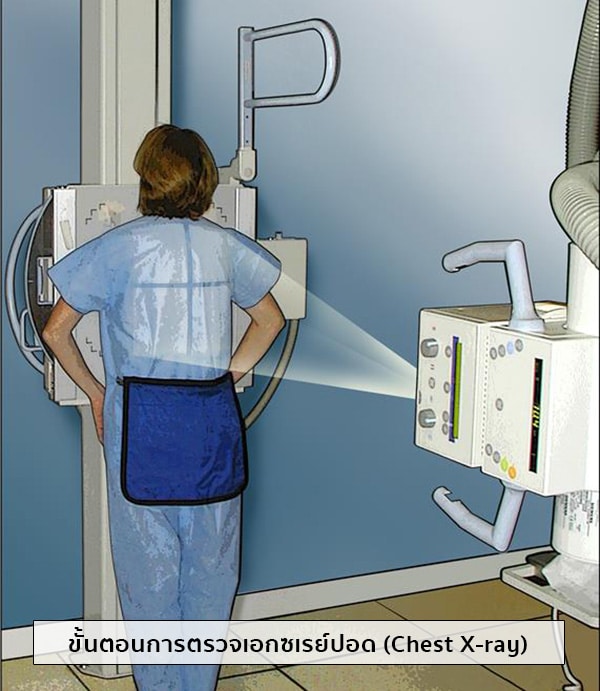

อันดับหนึ่ง ภาพถ่ายเกี่ยวกับภาพถ่ายเอกซเรย์ ที่ถูกรวบรวมและจัดทำโดยเว็บไซต์ cleverlearn-hocthongminh.edu.vn นอกจากนี้ยังมีภาพถ่ายที่เกี่ยวข้องกับ บริษัท อีเอ็กซ์พี ซิสเต็ม จํากัด, เสีย ภาษี 1 เปอร์เซ็นต์, หักภาษี ณ ที่จ่าย กี่เปอร์เซ็นต์, ทริปเปิ้ลเอ๊กซ์ 2 พยัคฆ์ร้ายพันธุ์ดุ 2005, ภาษี 7 เปอร์เซ็นต์ คือ, หักภาษี ณ ที่จ่าย 3 เปอร์เซ็นต์ ดูรายละเอียดด้านล่างค่ะ

ภาพถ่ายเอกซเรย์

ขอบคุณที่ต้องการเสริมสร้างความรู้ด้วยการอ่านบทความ ภาพถ่ายเอกซเรย์ ที่มีให้บริการที่ cleverlearn-hocthongminh.edu.vn ค่ะ ท่านสามารถแสดงความคิดเห็นและตรวจสอบบทความที่เกี่ยวข้องเพิ่มเติมที่ด้านล่างค่ะ หวังว่าจะเป็นประโยชน์ในการให้ข้อมูลที่น่าสนใจให้กับท่านค่ะ

Posts: ภาพถ่ายเอกซเรย์